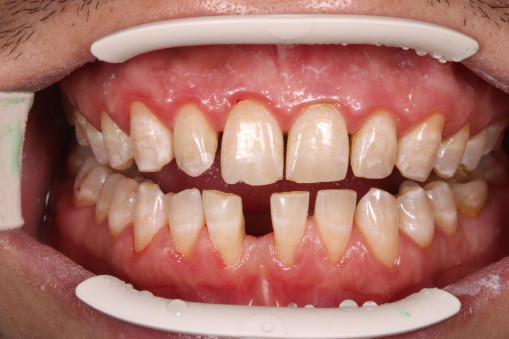

А прежде, чем вы посмотрите фотографии «до» и «после» лечения слизистой оболочки полости рта, проведенных в нашей клинике, хочу поблагодарить большое количество наших пациентов, которые поверили, прониклись нашей концепцией, и мы вместе, именно вместе победили болезни десны, гингивит и пародонтит!

До/после лечения